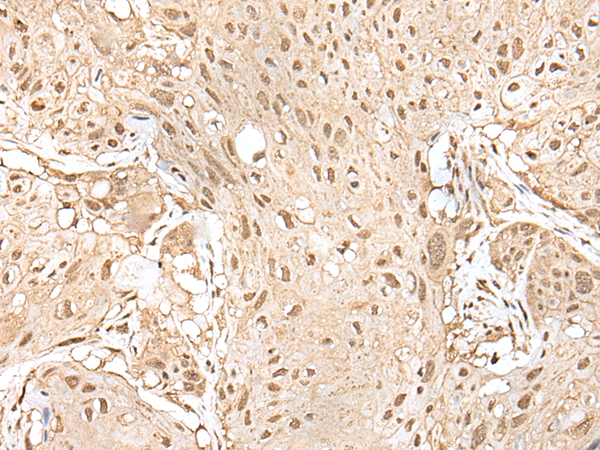

IHC positive control: |

Human esophagus cancer and human brain |

IHC Recommend dilution: |

25-100 |